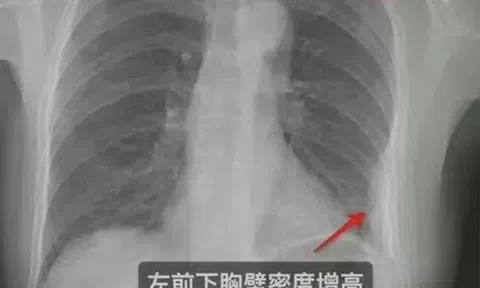

Đau đớn sau cái ôm của đồng nghiệp, cô gái nhận kết quả gây sốc khi đến bệnh viện kiểm tra

Chào hỏi lịch sự bằng một cái ôm, người đàn ông lại gây ra hậu quả không ngờ cho đồng nghiệp của mình.